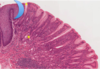

colon

Straight tubular glands (like test tubes in a rack). You don’t really find Paneth cells as a general feature. There’s a smooth surface epithelium